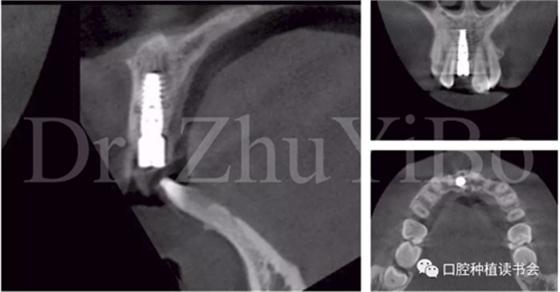

4.2.3 植入Nobel active種植系統(tǒng) RP 13mm種植體,植入扭矩大于45Ncm,初期穩(wěn)定性良好(圖11、圖12))。

圖11 使用Nobel active手用植入扳手精確控制植入方向

圖12 種植體初期穩(wěn)定性良好,注意與唇側骨板間的間隙

圖15術后即刻CBCT示:種植體軸向及深度良好